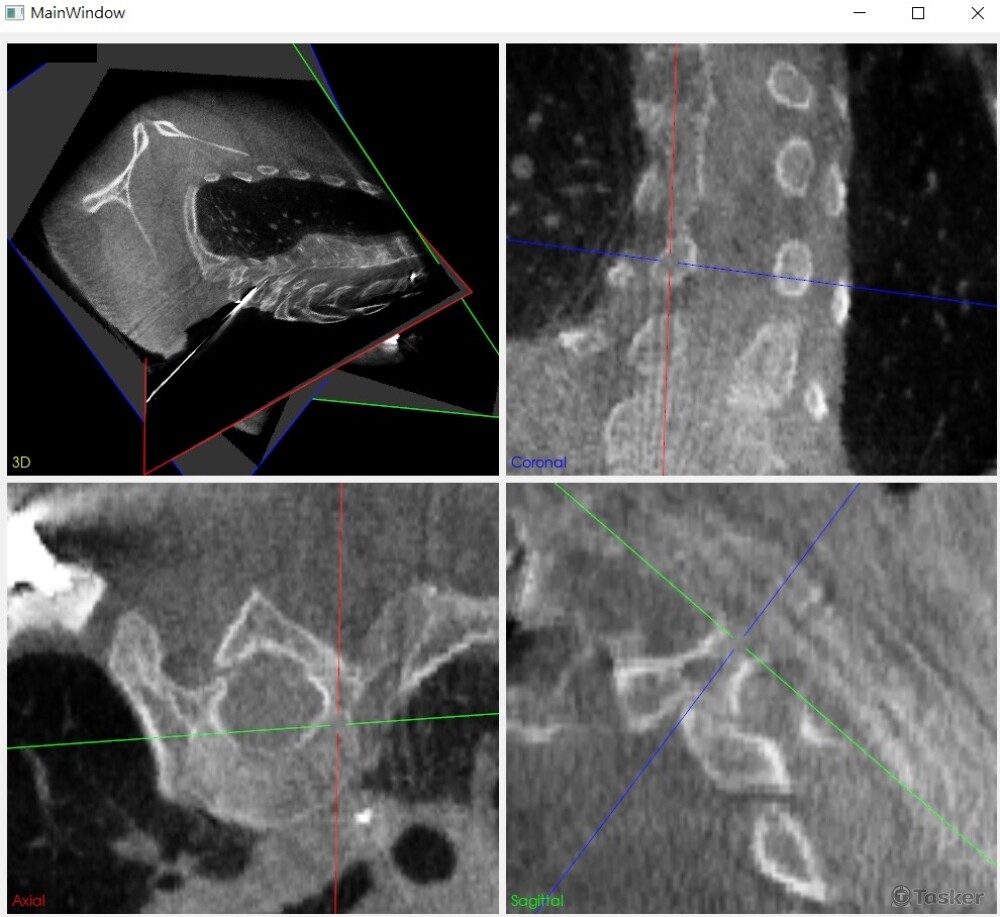

經過自由調整重切面,成為醫師易於辨識的角度視圖